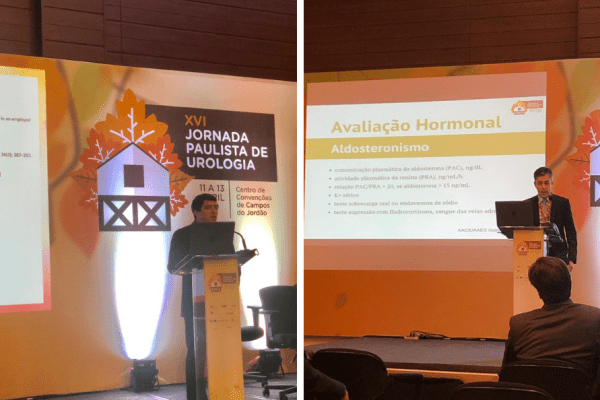

Urologistas da UROSERV ministram aulas durante a Jornada Paulista de Urologia

Os Drs. Fernando Tardelli e Samuel Santana ministraram aulas durante evento para urologistas, a Jornada Paulista de Urologia, realizado em Campos de Jordão. Dr. Fernando falou sobre Tumores Adrenais e Cistos Renais e…